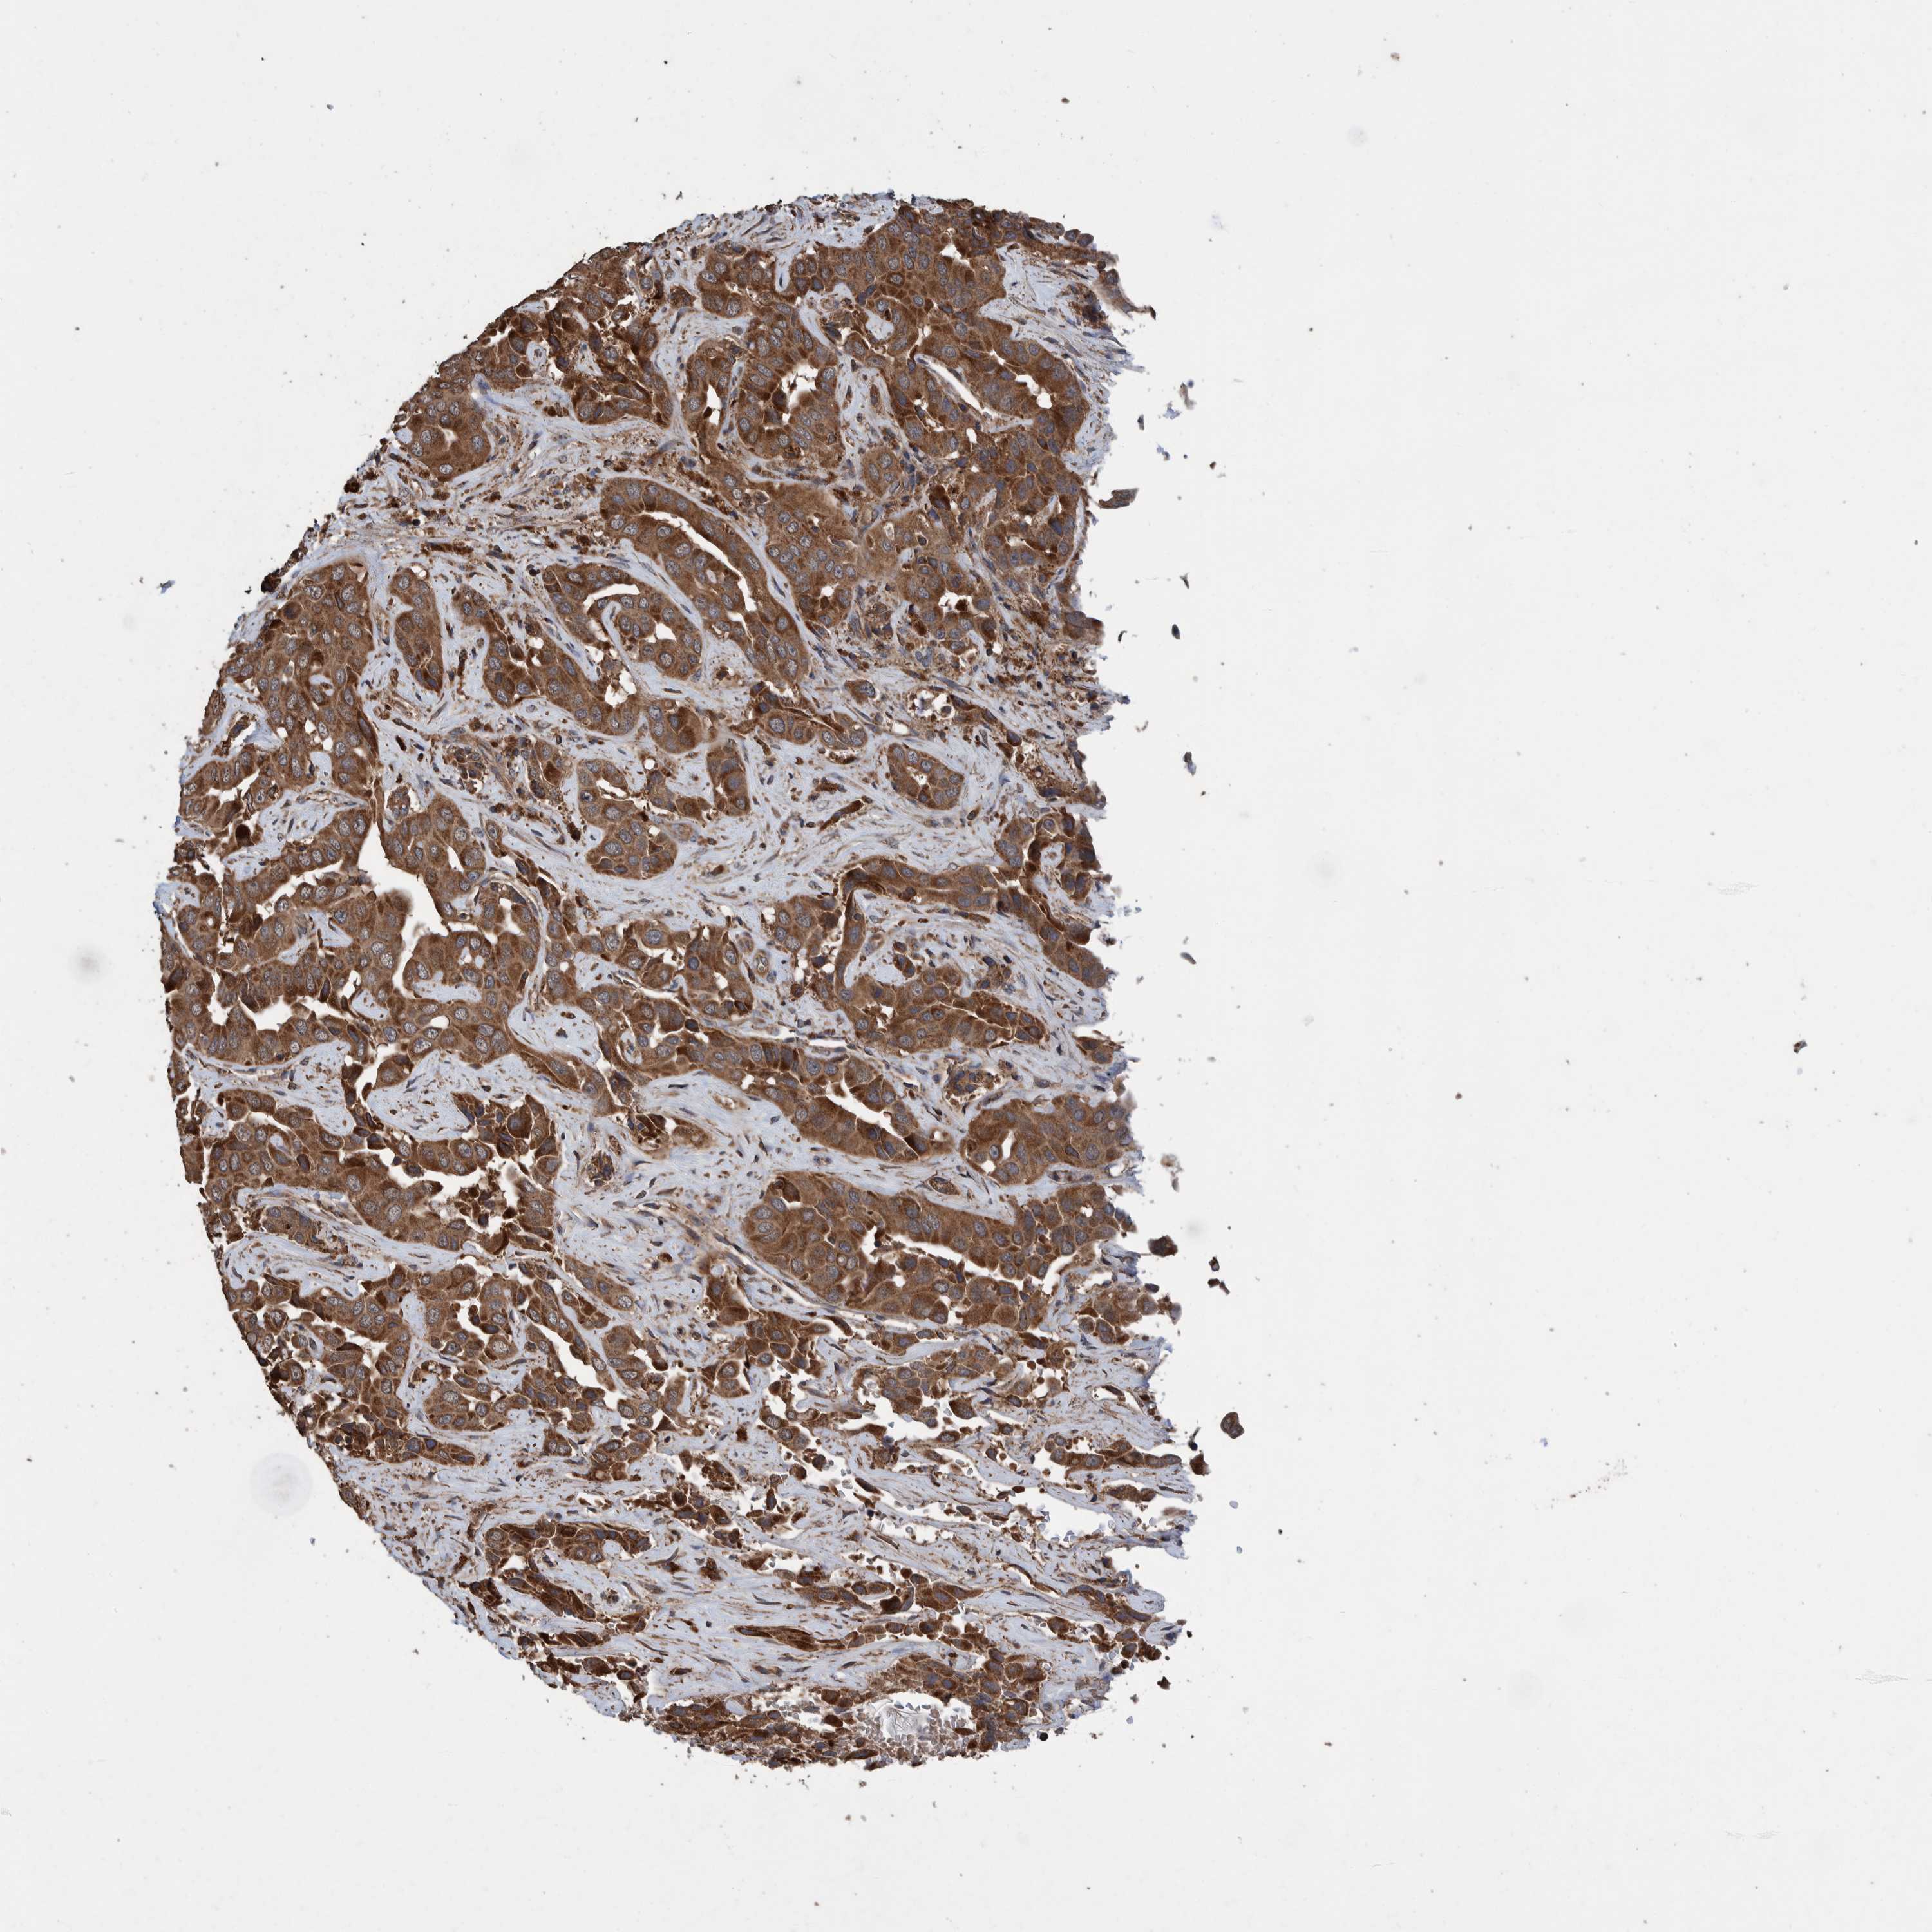

LIVER CANCER - Protein expressioni

A mouse-over function shows sample information and annotation data. Click on an image to view it in a full screen mode. Samples can be filtered based on level of antibody staining by selecting one or several of the following categories: high, medium, low and not detected. The assay and annotation is described here.

Note that samples used for immunohistochemistry by the Human Protein Atlas do not correspond to samples in the TCGA dataset.

Antibody stainingi

Antibody staining in the annotated cell types in the current human tissue is reported as not detected, low, medium, or high, based on conventional immunohistochemistry profiling in selected tissues. This score is based on the combination of the staining intensity and fraction of stained cells.

Each image is clickable and will lead to virtual microscopy that enables deeper exploration of all samples and also displays staining intensity scores, fraction scores and subcellular localization as well as patient and tissue information for each sample.

Antibody HPA023623

Antibody HPA066431

Staining

High

Medium

Low

Not detected

Intensity

Strong

Moderate

Weak

Negative

Quantity

>75%

75%-25%

<25%

None

Location

Nuclear

Cytoplasmic/membranous

Cytoplasmic/membranous,nuclear

Cholangiocarcinoma

Carcinoma, Hepatocellular, NOS